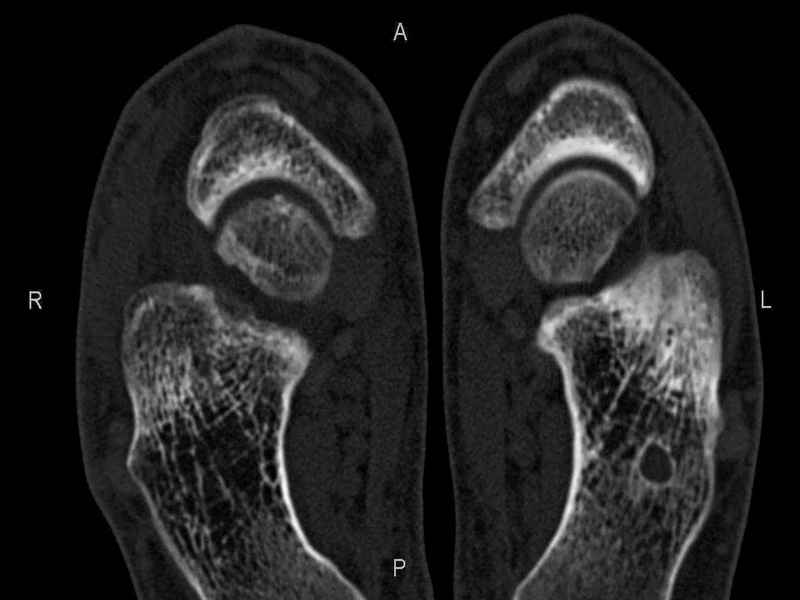

Рассекающий остеходрит + киста шейки тарана

Уважаемые коллеги, обратился за помощью пациент, мужчина, 25 лет. С жалобами на болевой синдром в области голеностопного сустава и среднем отделе стопы.

Травму отрицает. Со слов, болевой синдром в течении 1 года. Последние 1-1.5 мес периодически вынужден пользоваться костылями. После ограничения нагрузки боли уменьшаются. Соматически здоров. До появления болей активно занимался рукопашным боем.

На СКТ картина рассекающего остеохондрита блока таранной кости, киста шейки таранной кости с признаками импрессии суставной поверхности. А также - разрастания переднего края б\берцовой кости сопровождающиеся клиникой импиджмент синдрома.

Предполагаемый план лечения- удаление свободного фрагмента суставного хряща из трансмаллеолярного доступа с рассверливанием поверхности дефекта, кюретаж кисты шейки с заполнением полости биокомпозитом + дебридмент переднего отдела голеностопного сустава.

Прошу высказать своё мнение, за и против, предполагаемого плана лечения.

1. Есть ли необходимость в улучшении васкуляризации таранной кости (например подтаранный артродез).

2. Учитывая планируемое применение биокомпозитного цемента целесообразно ли заполнение им дефекта блока таранной кости с моделированием края суставной поверхности.